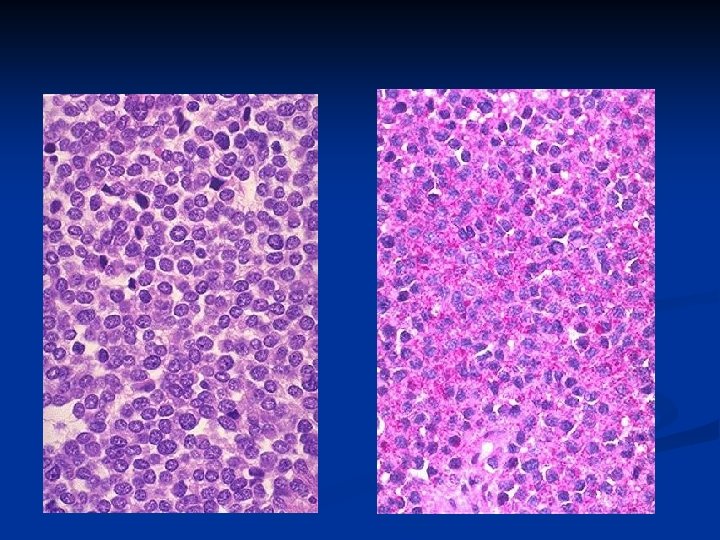

n n Microscopically, uniform, densely packed, tumor cells with a single, round or oval nucleus, indistinct cellular borders, and a size and appearance somewhat resembling lymphocytes (small round blue cells). The tumor cell cytoplasm characteristically contains PAS-positive glycogen granules. The tumor cells grow in sheets, sometimes with central necrosis, but without pattern, such as the rosettes typically formed by metastatic neuroblastoma.